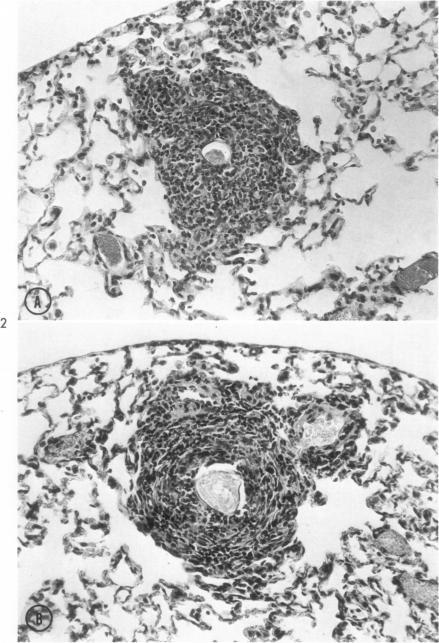

Perrotto J L, Warren K S

Am J Pathol. 1969 Aug;56(2):279-91.